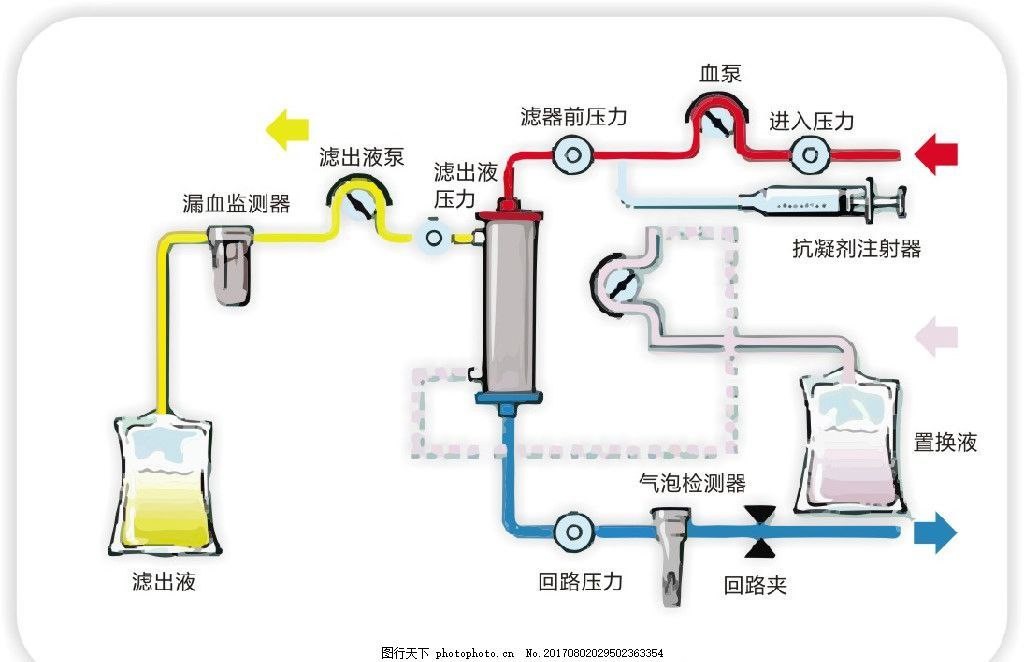

SC+血液透析系统

项目类型

医疗器械区

起投金额

8000USDT

每日释放:0.7

释放周期:150 天

已购: 3875

剩余: 0